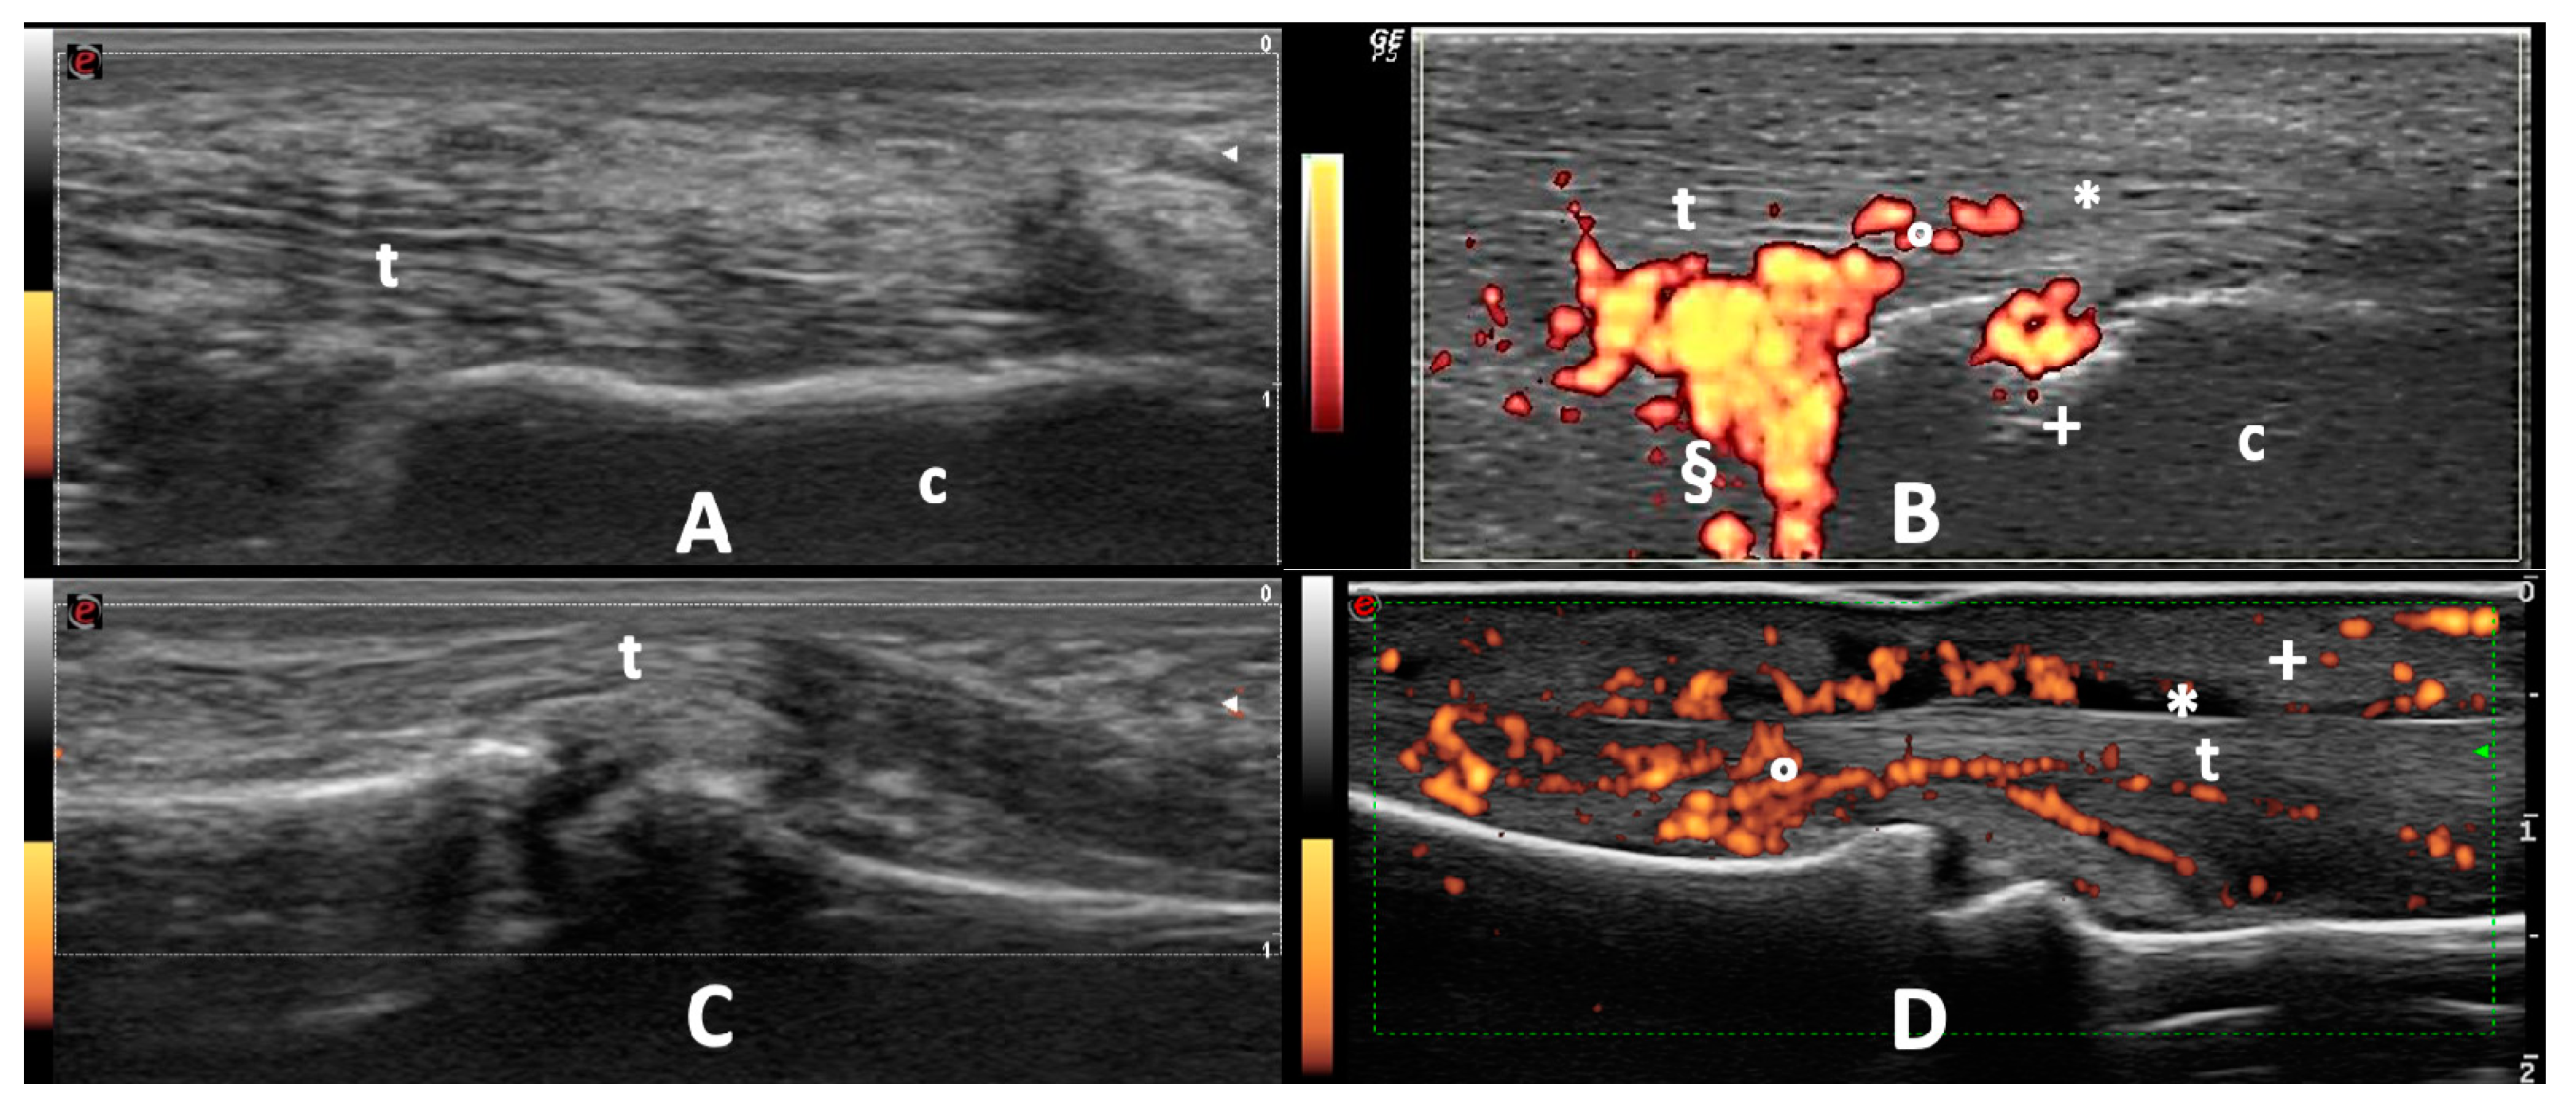

2.4.1. Peripheral Joints

2.4.2. Entheses and Tendons